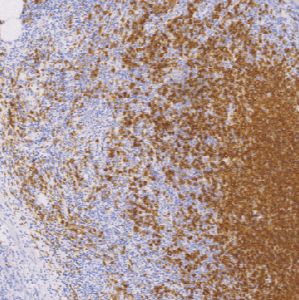

CD20鼠抗人CD20单克隆抗体

CD20抗原是一种非糖基化磷蛋白,分子量大约为33KD,表达在人的正常B细胞和恶性肿瘤B细胞中,并被认为在B细胞活化和分化中起受体的作用。据文献报道CD20抗原在外周血正常的B细胞中,淋巴结、脾脏、扁桃体、骨髓,急性白血病和慢性淋巴细胞白血病中都有表达。

- 阳性部位:胞膜

- 适用组织:石蜡切片

- 预处理:热修复